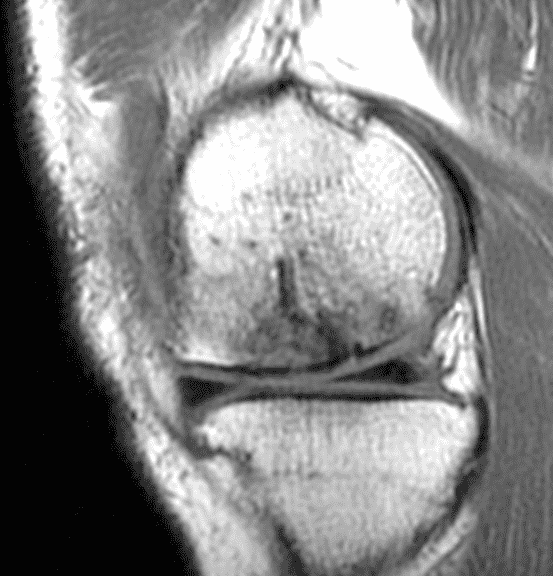

A 32-year-old man suffered a traumatic chondral injury to the medial femoral condyle that was treated with an osteochondral allograft 20 months previously. Representative images from a current knee MRI include (1A) coronal fat-suppressed fluid-sensitive and sagittal (1B) T1-weighted, (1C) proton density-weighted, and (1D) T2-weighted sequences. Are the post-operative MRI findings normal and expected, or abnormal and pathologic? Based on these images, would you characterize the procedure as a success or failure?

Figure 2: (2A) On the coronal image, the margins of the osteochondral graft are faintly visible (arrowheads). Both the graft and underlying bone show mild marrow edema, an expected finding. (2B) The T1-weighted image shows continuity of the marrow in the graft (asterisks) with the underlying bone, indicating osseous integration. A bioabsorbable pin (arrow) used for graft fixation is partly visible. (2C) The proton density-weighted image shows a low signal intensity seam (black arrow) between the native cartilage and transplant, as well as a defect in the subchondral bone plate of the graft (red arrow) where the pin was drilled, both normal findings. (2D) The T2-weighted image shows a smooth, congruent articular surface (arrows), restoring the normal anatomy, and a tiny subchondral cyst. No findings are present to suggest graft failure. The patient’s current symptoms were attributed to pathology elsewhere in the joint (not shown).

Successful osteochondral allograft procedure.